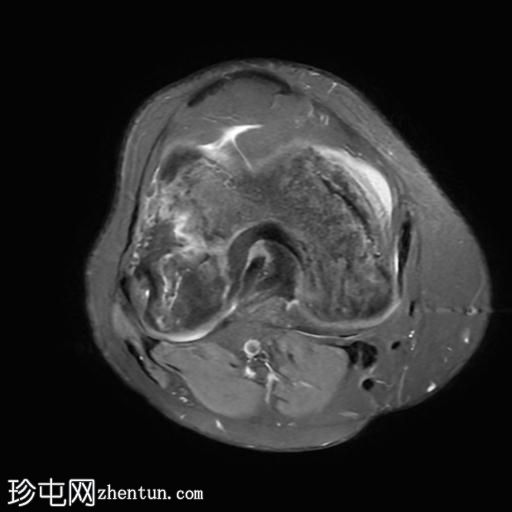

轴位PD脂肪抑制序列

在股骨远端和胫骨近端的髓腔内可见不规则的蛇形异常信号线。PD图像上,高信号线与骨髓内低信号线的内表面平行。

可见少量关节积液。

股骨远端和胫骨近端可见典型的骨梗死MRI表现。